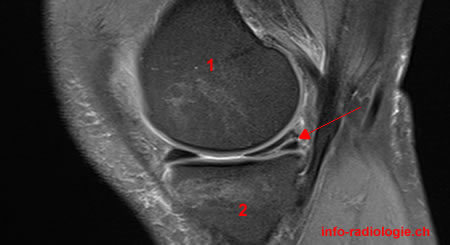

IRM du genou pour douleurs et hydarthrose récidivante: que voit-on?

Anse de seau du ménisque

Un patient s’est présenté aux urgence pour blocage aigu du genou, une IRM est réalisée que voit-on?

Anse de seau luxée dans l’échancrure intercondylienne